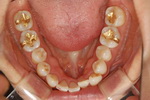

| ÃæÄ¡ ±ÝÀη¹ÀÌ¿Í ·¹Áø |